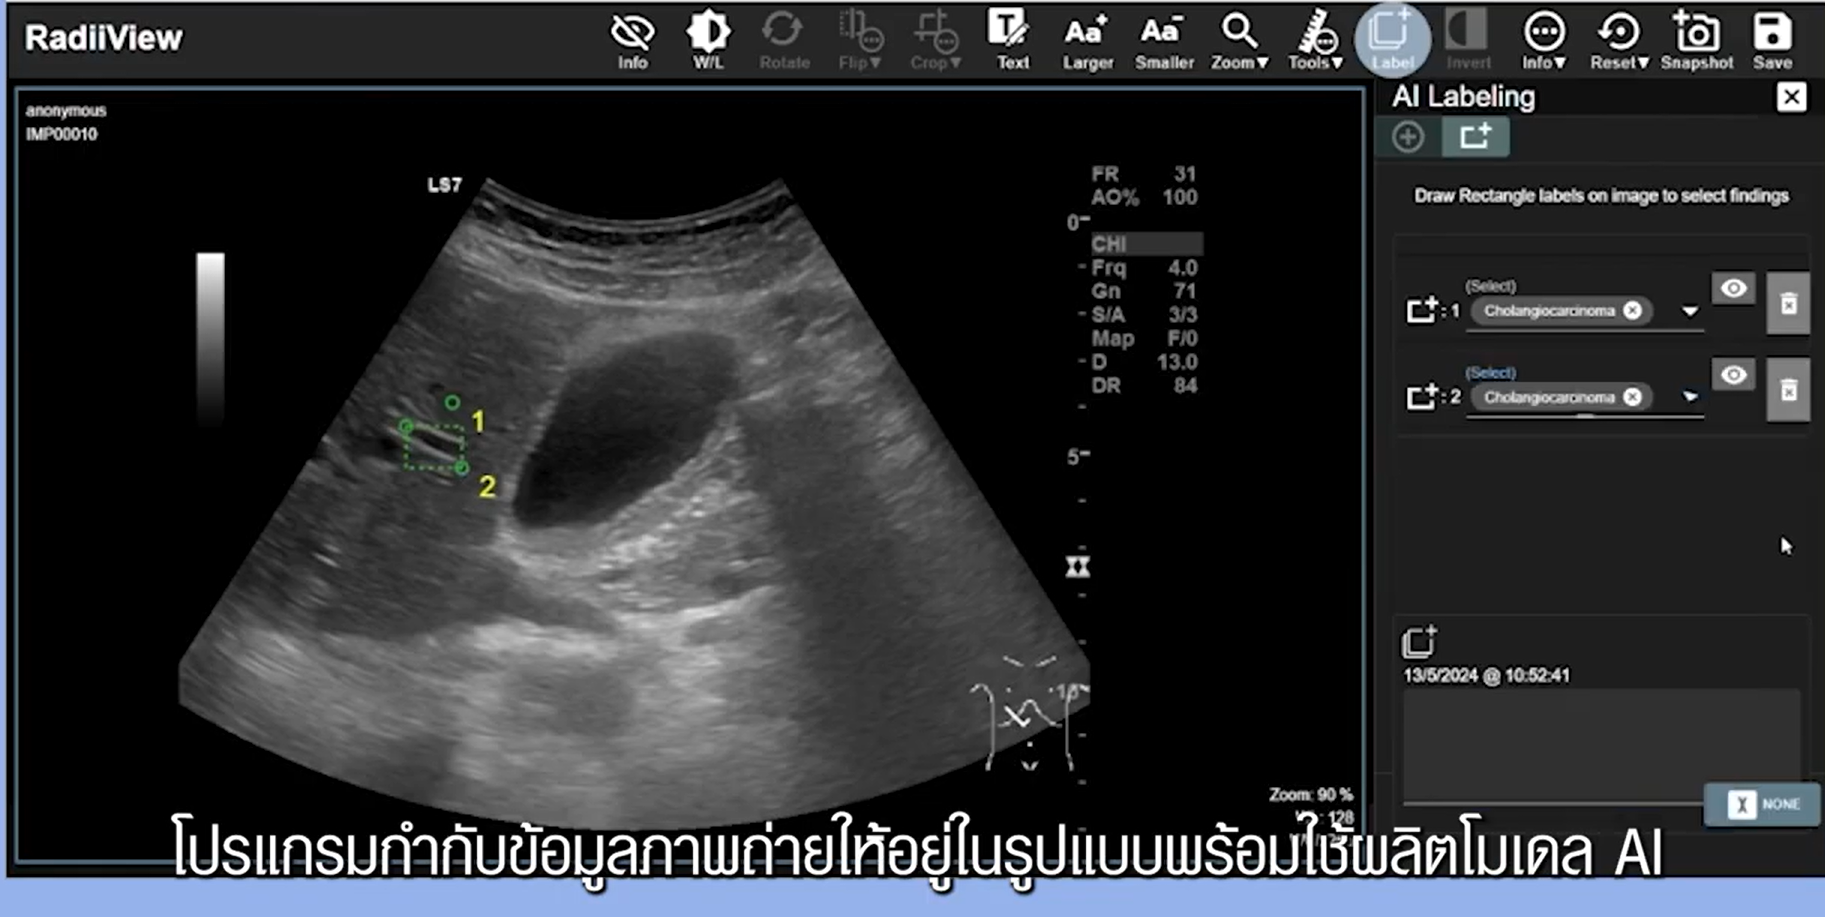

1. ส่วนบริหารจัดการข้อมูล (Data Management) รองรับการรวบรวม จัดเก็บ จัดทำรายการข้อมูลภาพทางการแพทย์อย่างปลอดภัยและเป็นระบบ มีการกำกับดูแลสิทธิ์การเข้าถึงตามหลักธรรมาภิบาลข้อมูล นอกจากนี้ นักวิจัยเนคเทค สวทช. ยังพัฒนา RadiiView ซอฟต์แวร์และคลาวด์แอปพลิเคชันสำหรับการกำกับข้อมูลภาพทางการแพทย์ (Annotation) ที่มีเครื่องมือช่วยให้แพทย์ระบุลักษณะสำคัญบนภาพได้อย่างแม่นยำ เพื่อสร้างชุดข้อมูล